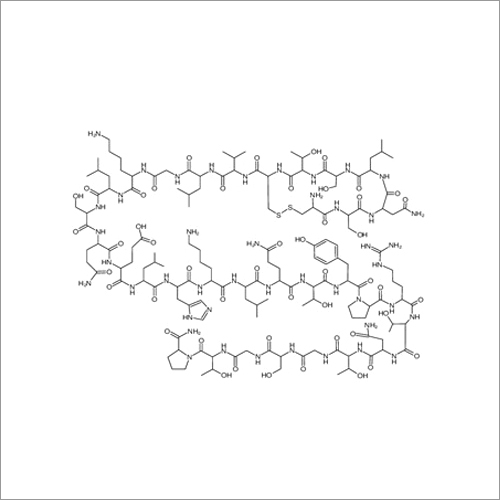

69558-55-0 थाइमोपेंटिन शुद्धता (%): > 99.0% (एचपीएलसी)

| रासायनिक नाम | Thymopentin |

| कैस नं | 69558-55-0 |